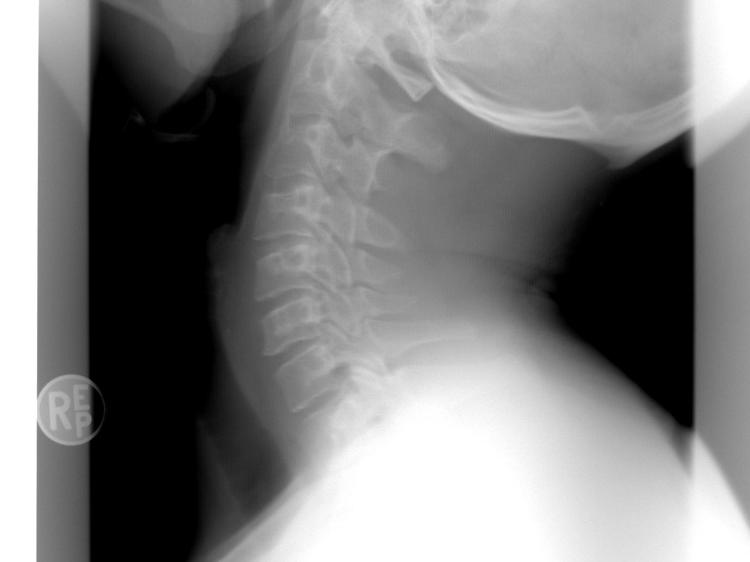

- 颈椎病症状加重,比如头晕呕吐频繁发作,影响正常生活。 就医时,医生可能建议做颈椎X线、CT、磁共振(MRI)明确颈椎病变,或做神经电生理检查排查神经问题,切勿自行判断病情。